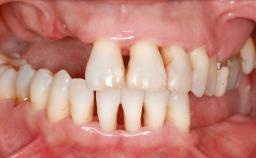

Iliac and Calvarial Bone Blocks for Onlay Grafting of a Severely Resorbed Edentulous Maxilla

A 45-year-old woman with a completely edentulous maxilla was referred to evaluate the possibility of rehabilitation with an implant-supported prosthesis. This patient was healthy and a non-smoker. She had been wearing a maxillary complete denture opposing a natural mandibular dentition since her twenties. This situation had resulted in progressive resorption of the alveolar ridge, repeatedly creating a need for relining the denture. Twenty years later, despite multiple adaptations and the use of “glues” the denture was unstable and causing the patient psychological and functional discomfort.